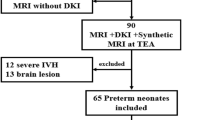

We performed a retrospective study of 24 term newborns of HIE whose neurobehavioral outcome was known on a follow-up visit to the Developmental Assessment Clinic of Children’s Hospital of Michigan. Clinical examination by a neonatologist data was available from electronic medical records. Out of the 24 with MRI, we found that DWI tractography scan was included in 15 newborns (gestation age = 39.2 ± 0.9 weeks and postconceptional age at MRI = 40.7 ± 1.3 weeks, Table 1). These 15 newborns were divided into three groups: